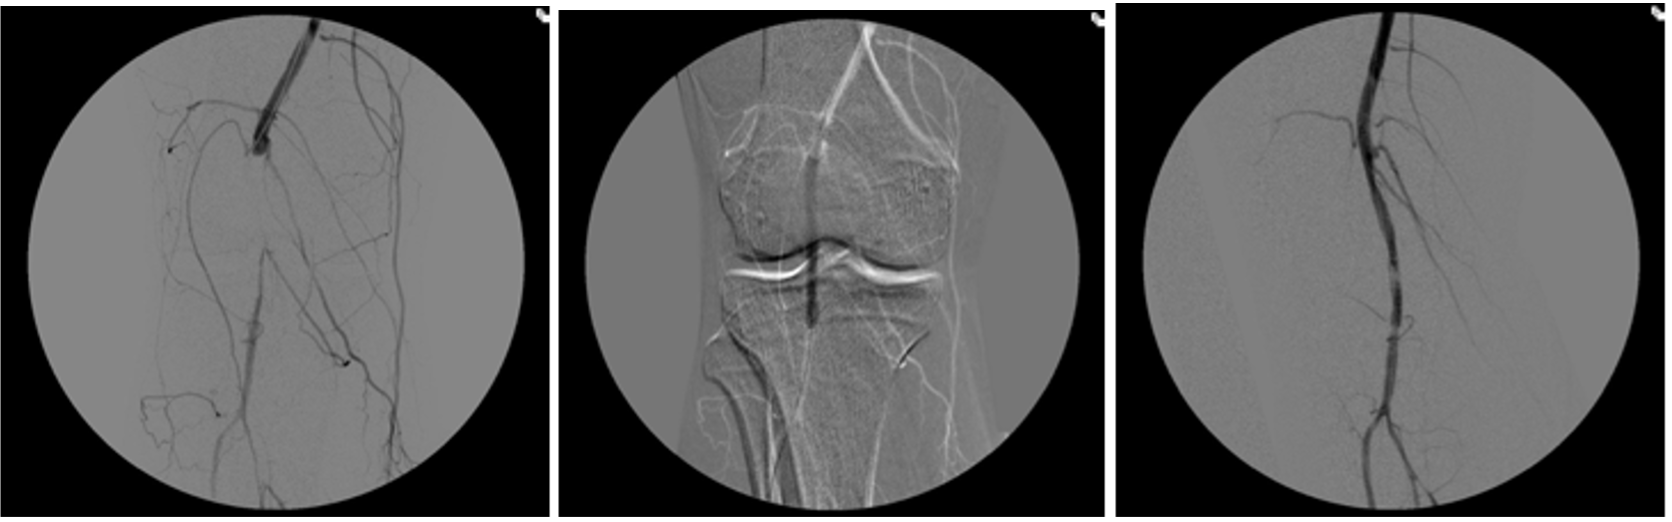

Many peripheral stenoses and occlusions are accessible by endovascular means. Among the endovascular procedures treatment of iliac and femoro-popliteal stenoses/occlusions are the most often used techniques. Thorough planing, proper use of endovascular tools and adherence to meticulous endovascular techniques are therefore of upmost importance for the success.